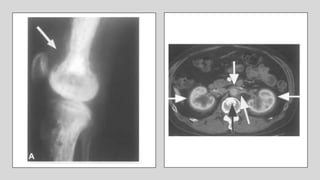

• Bone lesions can be asymptomatic or with mild pain and

affect distal limbs

• Skeletal (> 95%), Cardiovascular (50%), retroperitoneal (33%)

• CNS, diabetes insipidus, and/or exophthalmos in 20-30% of